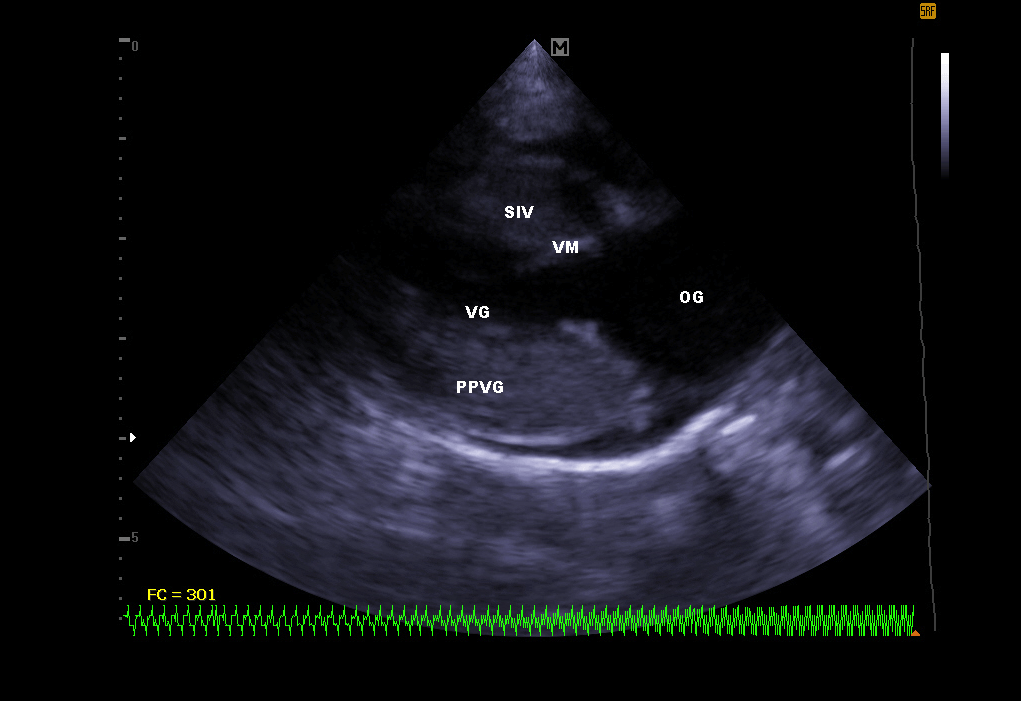

Echocardiography:

It makes it possible to visualize the different parts of the heart (walls, cavities, valves) and to identify any anomalies that prevent correct cardiac functioning. In case of heart failure, echocardiography also allows regular monitoring of cardiac morphology. It is then easier to readjust the treatment in place.